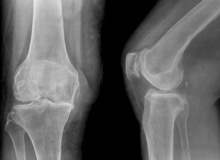

Yalancı gut, bir ya da daha fazla eklem yerinde aniden çıkan ve ağrılı şişlikle karakterize edilen bir eklem iltihabıdır. Nöbetler, günler veya haftalarca sürebilir. Yalancı gut, genel olarak yaşlı insanlarda ortaya çıkar ve çoğunlukla dizleri etkile